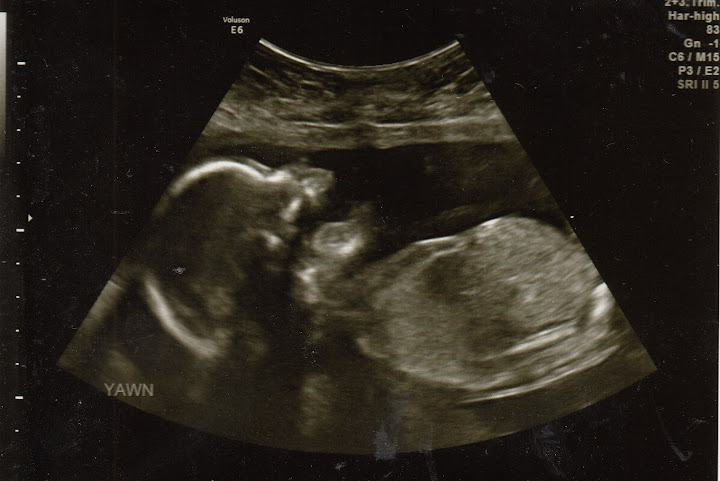

Apparently Joseph's frequent pointing, Stephen's declaration of, "Joseph! You are going to have a baby sister!", and my "awws" were boring the little miss, because she decided to yawn during the proceedings:

She's currently lying breech, weighs approximately 13 oz, and is due May 3rd. I find this to be hilarious because my sister Amy's birthday is also May 3rd AND she was breech when my Mom had her. Hopefully, my little girl won't decide to stay breech like my sister did. Do you hear that missy??? Breech is not an acceptable option!